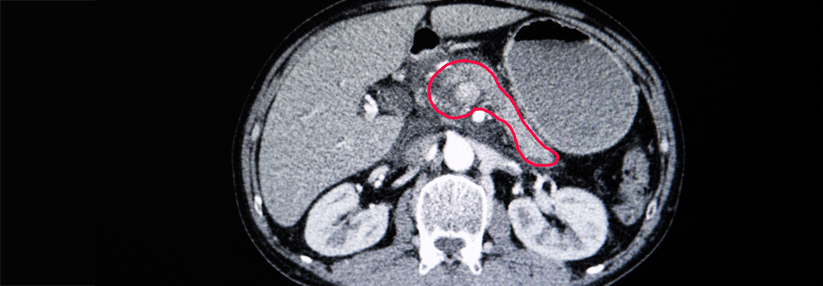

Als typisches Beispiel schilderte er den Fall eines 58-Jährigen. Der Patient in gutem Allgemeinzustand klagte über Müdigkeit, Abgeschlagenheit und Appetitlosigkeit. Auffällig war sein ikterisches Hautkolorit. Über drei Monate hinweg hatte der vormals übergewichtige Mann 35 kg Gewicht verloren. Das Labor ergab einen deutlich erhöhten Bilirubinwert bei mäßig…